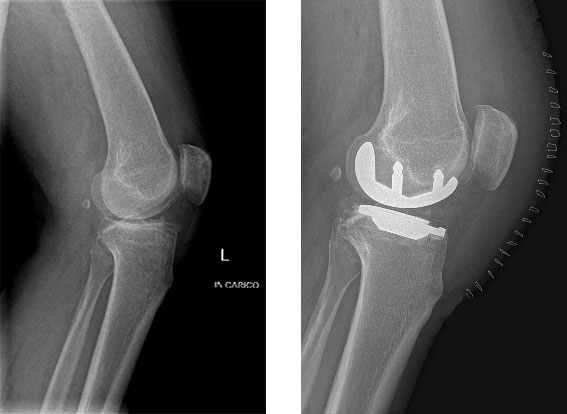

Paziente maschio di 65 anni, affetto da gonartrosi mediale sinistra, trattata con protesi monocompartimentale mediale di ginocchio con tecnica mini invasiva.

Radiografie